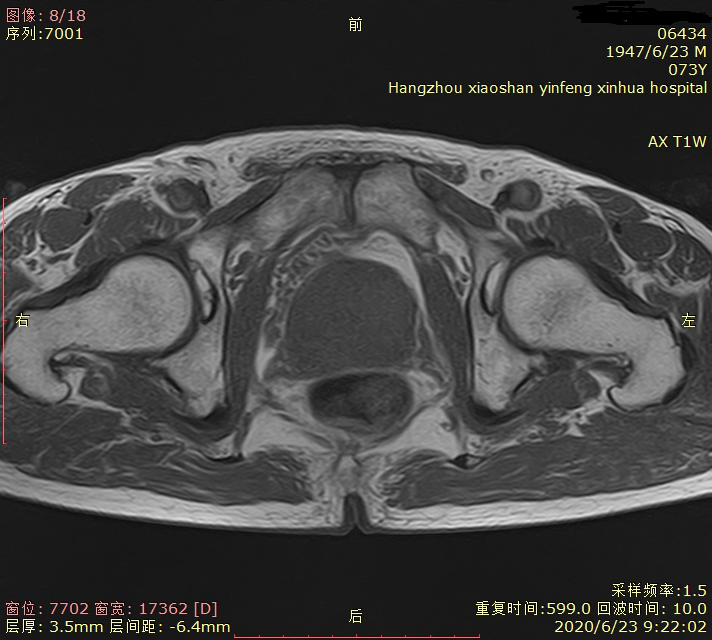

05 磁共振新技术的应用 前列腺弥散加权成像(DWI)对前列腺癌定性诊断有重要意义;可以作为PSA值异常后的常规筛查。